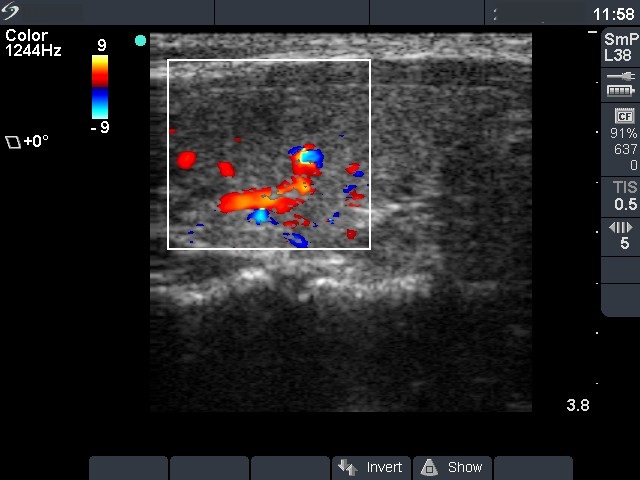

Follow-up investigation 18 months after first visit (ultrasonographic picture 6)

Patient on daily 5 mg methimazole therapy in euthyroid state

Left lobe, longitudinal scan, color Doppler mode. The vascularization is average.